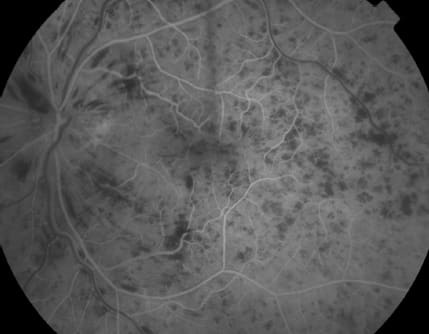

New pharmacologic therapies have forever changed the management of macular edema due to retinal vein occlusions (Figure 1). The lessons learned from the landmark 1984 Branch Vein Occlusion Study (BVOS)1 and 1995 Central Vein Occlusion Study (CVOS)2,3 need to be reconsidered in the light of data from recent randomized clinical trials of various intravitreal steroids and anti-VEGF agents for the management of macular edema due to RVO.

Figure 1. Central retinal vein occlusion with macular edema in the left eye of a patient with hypertension.